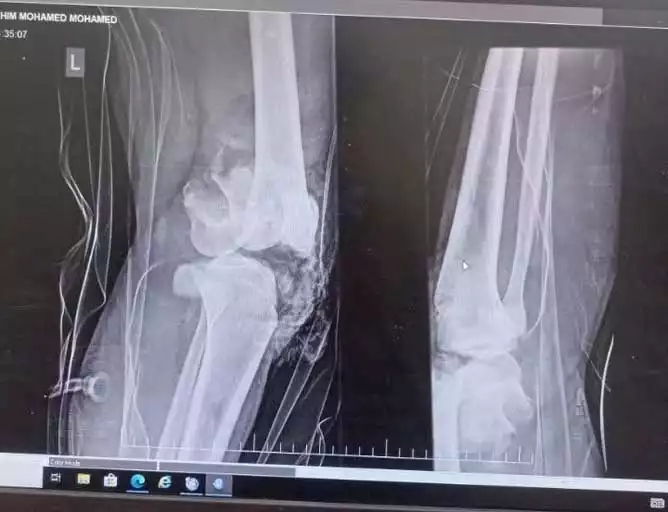

نجح فريق طبي متخصص بمستشفى القصاصين التخصصي في إجراء جراحة معقدة لعلاج كسر مفتت في مفصل عظم الفخذ لمريض شاب يبلغ من العمر 18 عامًا، وذلك بعد تعرضه لحادث أليم أدى إلى فقدان جزء من العظام.

وبناءً على ذلك، وضع الفريق الطبي خطة علاجية دقيقة تضمنت تثبيت الكسر باستخدام مسامير ضغط لتوصيل اللقمتين المفصليتين، مما ساهم في تحقيق التثبيت الأولي للعظام. كما تم إجراء محاذاة دقيقة للدوران والانثناء والبسط بين اللقمتين وجذع عظم الفخذ، مع استخدام أسلاك كيرشنر لتثبيت الوضع مؤقتًا، لضمان استقرار العظام قبل الانتقال إلى المرحلة التالية من العلاج.

ولتعزيز ثبات المفصل وتحقيق نتائج علاجية أفضل، قام الأطباء بتطبيق جهاز إليزاروف المفصلي، مع إبقاء مفصل الركبة مغلقًا خلال الأسابيع الأولى لضمان استقرار الإطار العظمي.